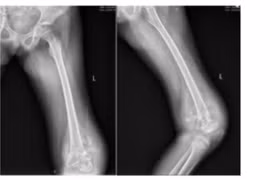

Lần đầu tiên tại Việt Nam, các bác sĩ khoa Ngoại Cơ xương khớp, Bệnh viện K đã thay khớp gối tăng trưởng thành công cho bệnh nhi 10 tuổi mắc ung thư xương.